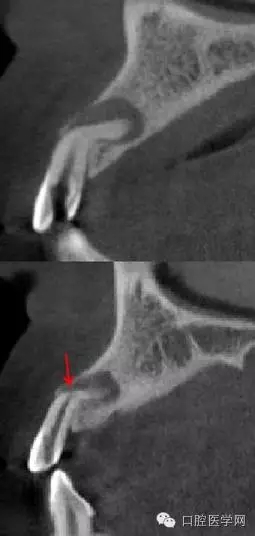

4.阻生牙

最常見于下頜第三磨牙

X線表現(xiàn):確定阻生牙的位置;確定阻生方向;牙根數(shù)目和形態(tài);阻生牙有無齲齒和根尖情況;與第二磨牙的關(guān)系;與下頜管的距離和磨牙后間隙的大小。